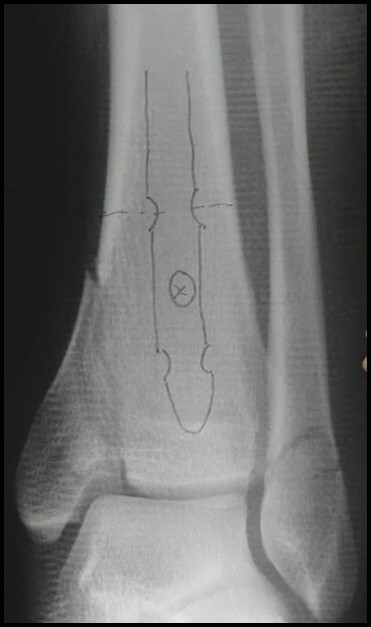

FX Diáfise da Tíbia

TTO Cirúrgico HIM

Acessos (3)

A

1. Transtendão patelar

2. Parapatelar medial

3. Suprapatelar (FX Proximal Tibia)

21

Q

Ponto de entrada Tibial

Medial à Espinha Lateral

Anterior à Superfície Articular

22

Largura da haste ?

• Régua

• 1 -1,5 mm < que a fresa

23

Comprimento da haste ?

• Proximal: 1 cm abaixo do platô

• Distal: Cicatriz fisária